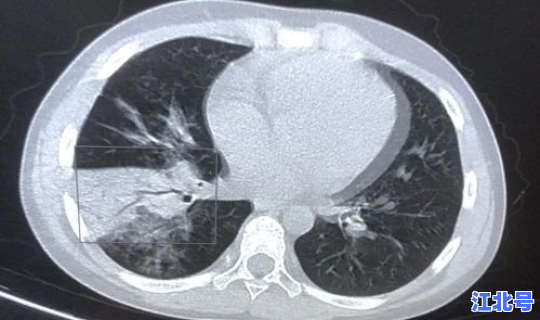

境外输入确诊病例1:中国籍。10月5日乘航班抵厦 。入境后即被集中隔离医学观察,6日核酸检测结果阳性,结合流行病学史、临床症状 、影像学表现和实验室检测结果 ,诊断其为新冠肺炎确诊病例,由市定点医院隔离诊治。其同航班旅客均已落实隔离医学观察措施。

境外输入确诊病例2-6:台湾居民 。10月5日乘航班抵厦。入境后即被集中隔离医学观察,6日核酸检测结果阳性 ,结合流行病学史、临床症状、影像学表现和实验室检测结果,诊断其为新冠肺炎确诊病例,由市定点医院隔离诊治。其同航班旅客均已落实隔离医学观察措施 。

境外输入确诊病例7-9:台湾居民。10月6日乘航班抵厦。入境后即被集中隔离医学观察 ,6日核酸检测结果阳性,结合流行病学史 、临床症状、影像学表现和实验室检测结果,诊断其为新冠肺炎确诊病例,由市定点医院隔离诊治。其同航班旅客均已落实隔离医学观察措施 。

境外输入确诊病例10:中国籍。10月4日乘航班抵厦。入境后即被集中隔离医学观察 ,6日核酸检测结果阳性,结合流行病学史、临床症状 、影像学表现和实验室检测结果,诊断其为新冠肺炎确诊病例 ,由市定点医院隔离诊治 。其同航班旅客均已落实隔离医学观察措施。

境外输入确诊病例11:美国籍。10月5日乘航班抵厦 。入境后即被集中隔离医学观察,7日核酸检测结果阳性,结合流行病学史、临床症状、影像学表现和实验室检测结果 ,诊断其为新冠肺炎确诊病例,由市定点医院隔离诊治。其同航班旅客均已落实隔离医学观察措施。

境外输入确诊病例12:台湾居民 。10月2日乘航班抵厦。入境后即被集中隔离医学观察,7日核酸检测结果阳性 ,结合流行病学史 、临床症状、影像学表现和实验室检测结果,诊断其为新冠肺炎确诊病例,由市定点医院隔离诊治。其同航班旅客均已落实隔离医学观察措施 。